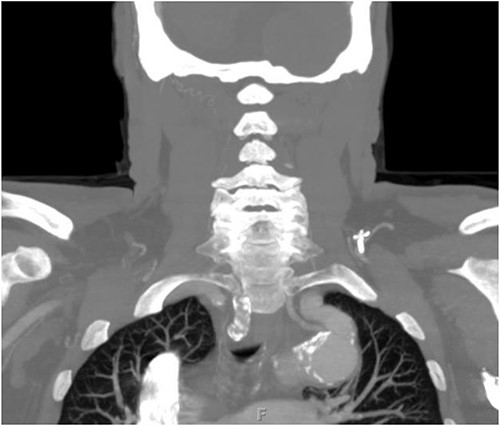

The patient is a 70-year-old male with an incidental finding of a proximal LSA aneurysm on computed tomography (CT) angiography of the chest performed for shortness of breath. He had no dysphagia, neurologic or vascular occlusive symptoms. He had no history of trauma or known congenital anomaly. The aneurysm had a maximal diameter of 3.4 cm and was located at the origin of the artery (Fig. 1). An aberrant left vertebral artery and hypoplastic right vertebral artery were also identified. The left vertebral artery originated from the aortic arch proximal to the LSA takeoff (Fig. 2) and provided dominant posterior cerebral circulation.

Preoperative CTA demonstrating LSA aneurysm; located at the origin from the aortic arch.

Preoperative CTA demonstrating aberrant left vertebral artery originating from the aortic arch, just proximal to the LSA.